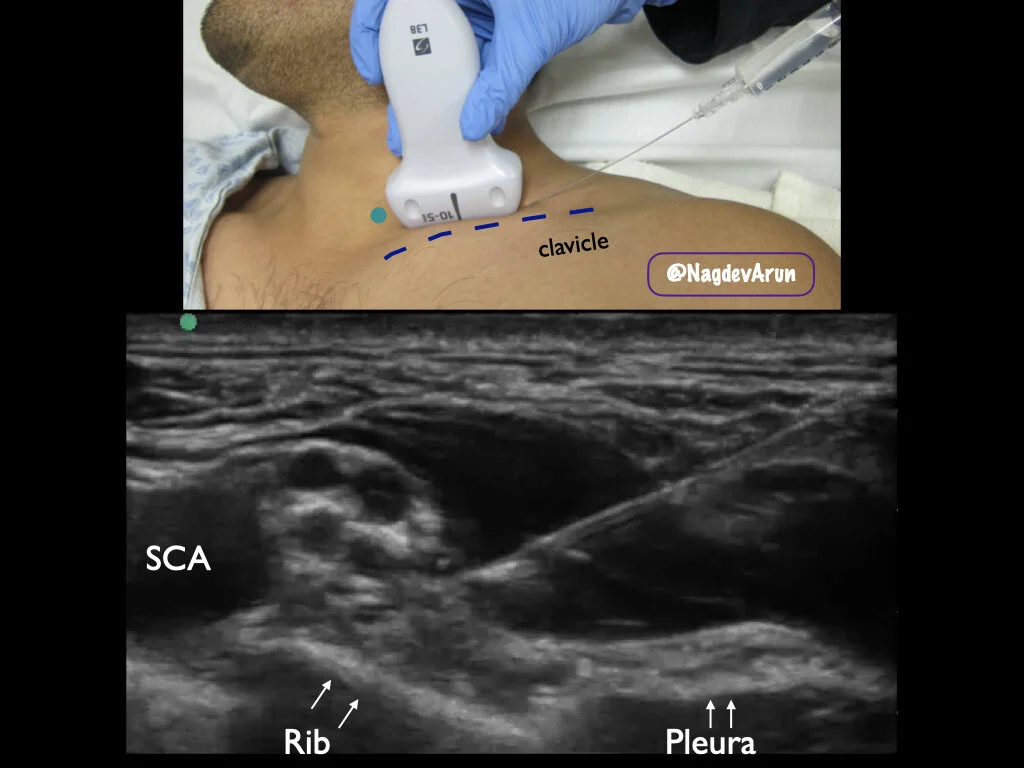

INDICATIONS : deltoid abscess incision and drainage, humeral fracture pain control, elbow dislocation/reduction, distal radius fracture/reduction, etc.

Recommend: use a Blunt Tip block needle and inject with LOW PRESSURE. Always stay away from the nerve if possible. We like using the first rib as a backstop. Anesthetic type and amount should be based on the case (always be aware of maximal dosing).